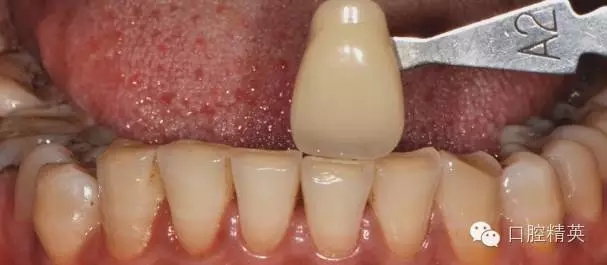

術(shù)前比色